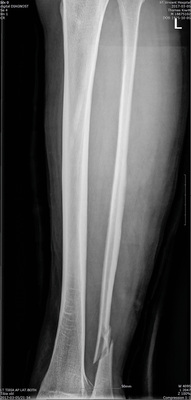

Die Diagnose einer distalen Fibulafraktur mit Syndesmosenverletzung sowie Verletzung des Ligamentum deltoideum wurde dem Patienten mitgeteilt (  Abb. 5 ).

Auch wurde er über die Indikation zur operativen Versorgung aufgeklärt, die jedoch aufgrund der starken Schwellneigung zunächst verschoben wurde. Der Patient wurde mit Schmerzmedikation und Thromboseprophylaxe mit einer Gipsschiene versorgt an Krücken eingeschränkt mobil ins Hotel entlassen.

Die Röntgenbilder wurden telemedizinisch übermittelt. Auch akzeptierte die Klinik ein von International SOS zur Verfügung gestelltes, in Englisch ausgestelltes „Fit-to-fly-Zertifikat“ für die Luftfahrtgesellschaft.

Mit dem Patienten wurden die Transportempfehlungen abgesprochen. Für die Strecke vom Hotel zum Flughafen wurde ein Liegentransport im Krankentransportwagen vorgeschlagen, ab dem Flughafen ein Rollstuhlservice bis zum Sitz (Wheelchair Cabin Seat, WCHC) und Hilfe beim Gepäck. Der Patient war in einer Gipsschiene bei gegebener Schwellneigung und entsprechender Thromboseprophylaxe und Schmerzmedikation im Business-Class-Sitz adäquat versorgt. Eine aufrechte Sitzposition bei Start und Landung für ca. 45 Minuten waren dem Patienten zumutbar. Für Deutschland war wieder ein Liegendtransport vom Flughafen zur BG-Klinik geplant.

Die vom Patienten gewünschte heimatnahe Klinik der Berufsgenossenchaften wurde kontaktiert und die Vorbefunde telemedizinisch übermittelt. Man akzeptierte den Patienten zur Aufnahme am Folgetag nach der Reise über die Ambulanz. Bis zur endgültigen Versorgung mussten noch einige Tage zum Abschwellen zugewartet werden.

Prinzipiell wäre eine finale Versorgung in Korea möglich gewesen. Aufgrund der kulturellen Unterschiedlichkeit und zumindest mit dem pflegerischen Personal eingeschränkter Kommunikationsfähigkeit sowie der Isolierung in Bezug auf soziale Kontakte wurde stattdessen einer primären konservativen Stabilisierung, Antikoagulation und unbegleitetem Transport im Linienflugzeug sowie der finale Versorgung heimatnah der Vorzug gegeben. Die telemedizinische Übermittlung der Befunde erleichterte die Vorabplanung im aufnehmenden Krankenhaus erheblich.